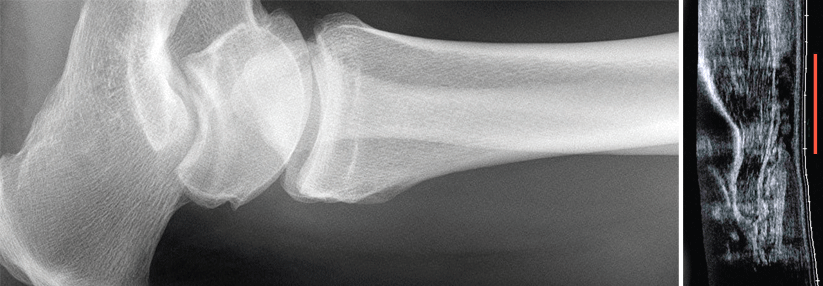

Gerissene Achillessehne ruhig nähen

Achillessehnenrupturen machen vor allem als Sportverletzung von sich reden. Statistisch gesehen könnte der konservative Ansatz überzeugen. Doch so…

Orthopädie , Sportmedizin